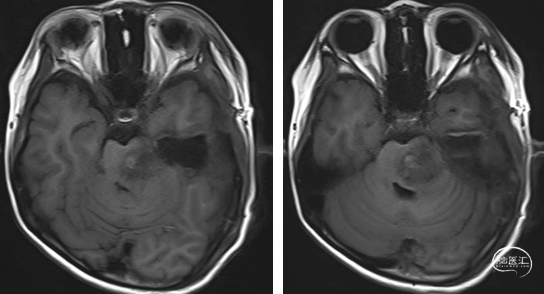

2023年9月13日 MRI T2